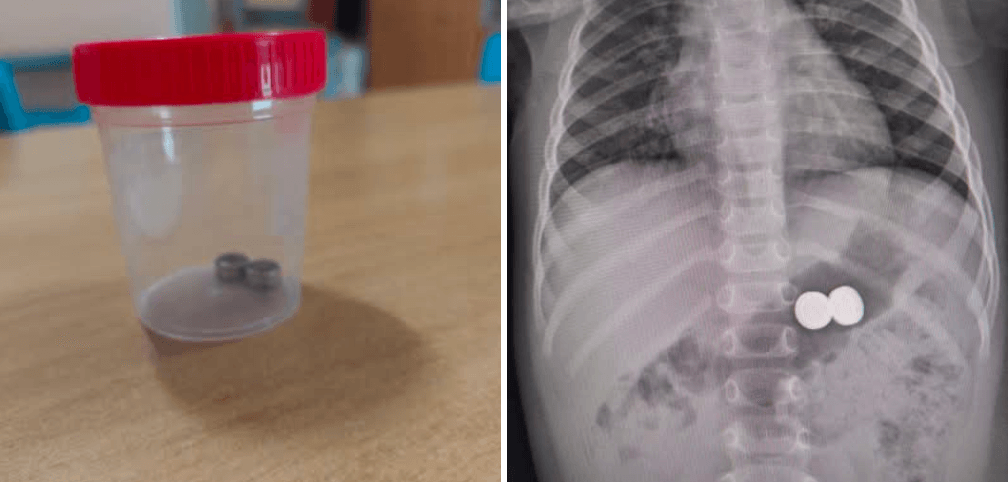

Bambina di 1 anno ingerisce batterie a bottone, operata d’urgenza

Una bambina di un anno è stata condotta d’urgenza all’ospedale Garibaldi-Nesima, dopo aver ingerito due batterie a bottone. Il pronto…

Bimba catanese di 18 mesi in gravi condizioni dopo aver ingerito una batteria a bottone

Una bambina di diciotto mesi è ricoverata in gravi condizioni presso il reparto di Rianimazione dell'ospedale Garibaldi-Nesima di Catania. L'oggetto…